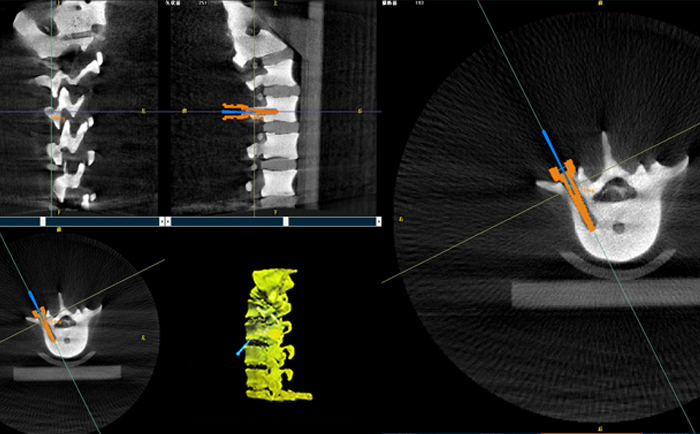

在一臺機器人輔助下的脊柱手術中,使用三維C形臂與機器人匹配,僅15秒左右就能獲得患者病變脊柱部位的高清3D圖像,機器人輔助手術可準確定位病變部位、置入椎弓根螺釘位置等。

目前脊柱外科應用最廣泛的還是機器人輔助置入椎弓根螺釘。主刀大夫可以通過該3D圖像確定手術中椎弓根螺釘?shù)倪M釘點、置釘方向以及置釘深度。緊接著,在機器人手術系統(tǒng)的導航下,該機械手臂能夠準確移動到定位椎弓根螺釘?shù)戎冕斘恢?,醫(yī)生只需要在置釘部位切開一個1cm切口,沿著機械臂所指方向鉆入導針,并沿導針按置入椎弓根即可,從而使椎弓根螺釘能夠以最理想化的方式打入,保證患者的安全和手術有效性。